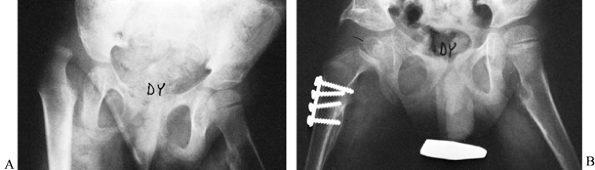

obturator neurectomy would also be performed (Fig. 177.8).

Figure 177.8. A: A 9-year-old child with spastic cerebral palsy and severe dislocation of left hip. B: The same child after Chiari osteotomy and varus osteotomy.